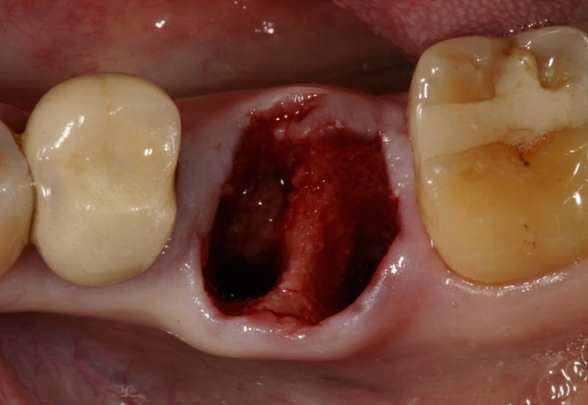

拔牙後傷口

拔牙當天立即植體植入,傷口縫合